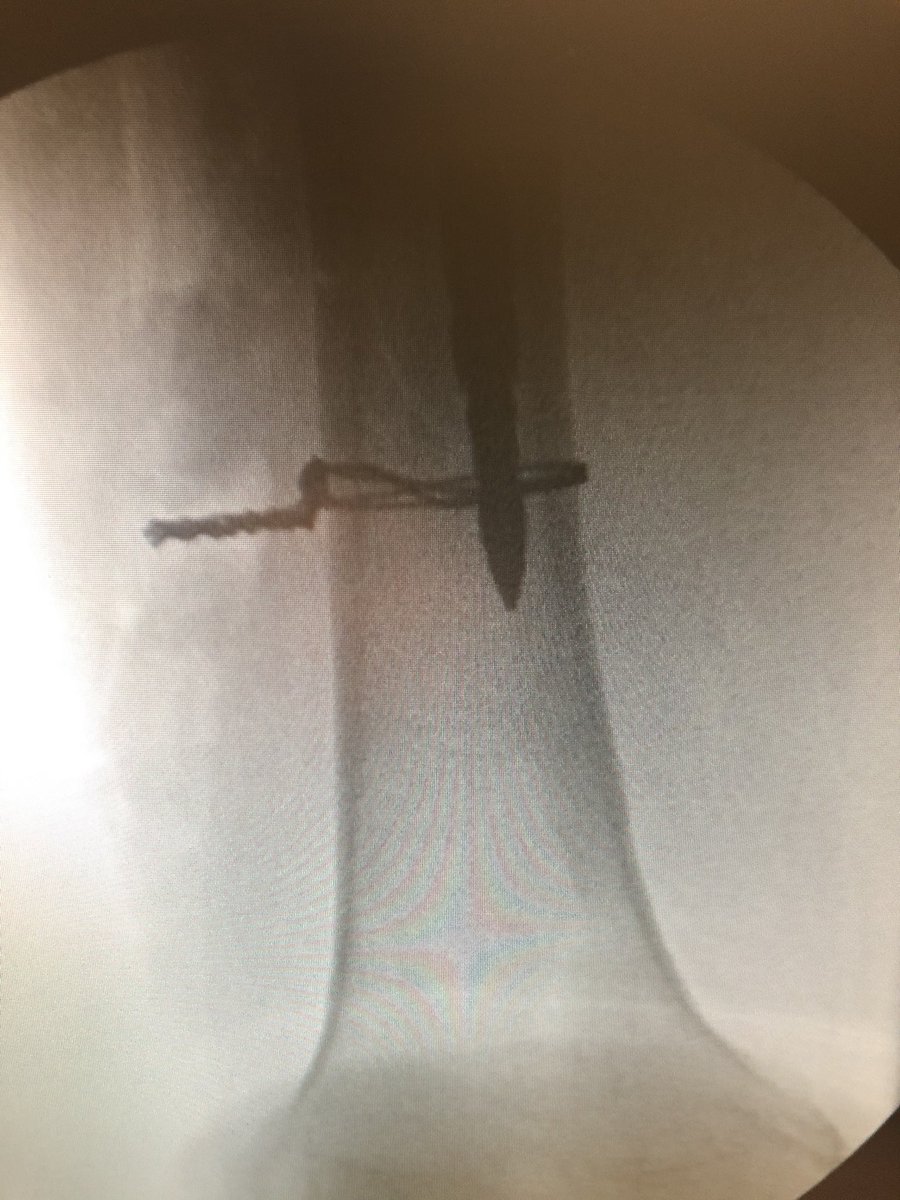

Distal fragments identified with David A. Molho, M.D. . Fx all the way to distal lateral metaphysis with comminution there. Canal re-established over a long reamer and wired anatomically.

Distal fragments identified with <a href="/TotalHipKnee/">David A. Molho, M.D.</a> . Fx all the way to distal lateral metaphysis with comminution there. Canal re-established over a long reamer and wired anatomically.